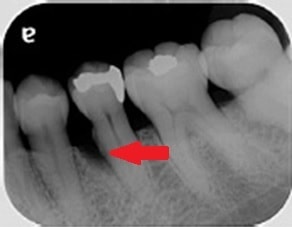

治療前は、赤の矢印で示すように歯の周りに黒いところがあることが分かるかと思います。簡単に言うと、骨が溶けた状態になります。

通常、歯周ポケットと呼ばれる歯と歯茎の間の溝は3㎜程度なのですが、10㎜を超える歯周ポケットがありました。CTは、手術前に骨の欠損形態を的確に把握できるため、歯周病の治療にも非常に有用です。

歯周病の基本的な治療を行い、その後に、歯周組織再生療法という失われた歯の周りの組織を再生させる手術を行って約2年のレントゲンになります。

青の矢印で示すように、治療前黒かった部分が、白くなってきていることが分かるかと思います。失われた歯周組織の再生が促されていることが推測されます。CTにおいても歯の周囲の失われた骨が再生してきていることが、分かるかと思います。